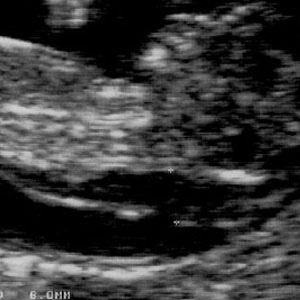

هنگامی که جنین بین 45 تا 84 میلیمتر طول دارد، NT کمتر از 3.5 میلیمتر طبیعی است. NT با رشد جنین افزایش می یابد. تصاویر زیر مقادیر مختلف NT را نشان می دهد.

NT= 6 mm:

- با افزایش NT نوزاد بیشتر در معرض خطر سندرم داون و سایر مشکلات کروموزومی قرار می گیرد.

- جنین با NT=6 میلیمتر در معرض خطر زیادی است. همچنین این جنین در معرض مشکلات قلبی و اختلالات کروموزومی نیز می باشد.

- خوشبختانه بیشتر جنین ها در این حد مایع پشت گردنی ندارند.